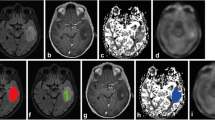

Perfusion MRI

The rCBVmax ratios in the PET hotspot and the rCBV ratios in the large tumor ROI for each case (n = 24) are shown in Table 1. The mean rCBVmax in PET hotspot regions for the whole sample was 3.19 ± 1.66 (range 0.92–8.27) (Fig. 1a). The mean rCBV in the large tumor ROI was 0.99 ± 0.77 (range 0.28–4.24), which was significantly lower (P = 0.0001). Regions with rCBVmax corresponded to hotspot regions on PET in all cases. The correlation between rCBVmax ratios in the hotspot region and HS/cortex ratios is shown in Fig. 1b (Spearman’s r = 0.19, P = 0.38). There was a significant difference in mean rCBVmax between gliomas grade II and gliomas grade III (P = 0.04), but not between enhancing and non-enhancing lesions (P = 0.34).

In the present study, we investigated 24 patients with suspected LGG by morphological MRI, physiological MRI and MET PET prior to surgery. Our aim was to define the correlation between MET uptake and perfusion and diffusion abnormalities in these tumors at the time point of radiological diagnosis. We found that regions with rCBVmax corresponded with hotspot regions on PET in all tumors. However, in spite of a consistent topographical overlap between hotspot on MET PET and areas with maximum tumor perfusion, there was no significant positive correlation between rCBVmax and highest MET uptake. Our results are in contrast to a previous study, reporting a positive correlation between rCBVmax and maximum MET uptake and indicating a close link between amino acid transport in the tumor and vascularity [31]. This discrepancy may be partly due to the different study populations and methodologies, but also to the general difficulties of measuring subtle differences in regional perfusion in non-enhancing infiltrating tumors [32]. It is difficult to select a ROI with high intra- and inter-observer reproducibility in LGG, since perfusion images are noisy compared to both morphological images and MET PET scans. Susceptibility artifacts with signal loss and adjacent signal increase, simulating perfusion increase, may also disturb perfusion images. In addition, high perfusion values in vessels and adjacent cortex may be difficult to differentiate from increased tumor perfusion. Therefore, pMRI alone appears to be unsuited to replace MET PET in providing reliable baseline data on tumor vascularity. This is further illustrated by our perfusion measurements calculated within a large tumor area and without prior knowledge of MET PET, which were significantly lower than the co-registered PET/MRI measurements. The present study shows that the co-registered measurement of rCBVmax and MET uptake is a reliable way to define perfusion abnormalities in LGG (illustrated in Fig. 3).

Patient 8. Preoperative MET PET and MRI of a right-sided frontal oligodendroglioma grade II in a 31-year-old female. a MET PET shows the hotspot region of the tumor. b T2-weighted FLAIR MRI shows a high signal intensity tumor. c T1-weighted contrast-enhanced MRI shows minimal contrast enhancement in the tumor area. d DSC perfusion MRI with rCBV color map shows high perfusion in the tumor area. e DSC perfusion MRI with rCBV grey-scale map shows high perfusion in the region corresponding to the PET hotspot. The ROIs in the tumor and in the contralateral normal appearing white matter are marked. f dMRI where the MDmin value in the region corresponding to the PET hotspot is lower than MD in the medial portion of the tumor (but minimally increased compared to normal appearing contralateral white matter)